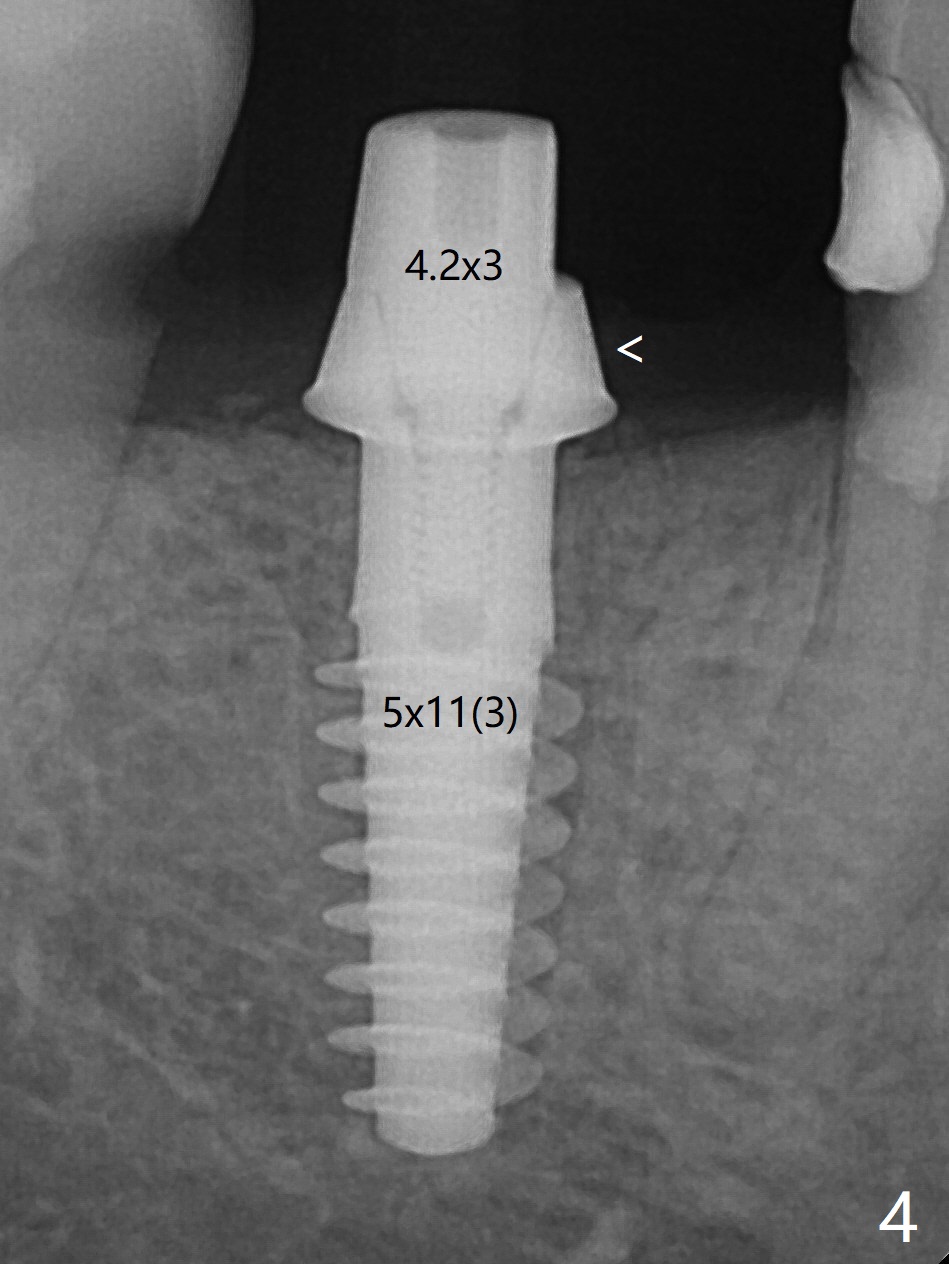

A 5x12 mm SM implant with periimplantitis at #30 is removed with a 5/6 mm trephine bur, small elevator and implant driver. A 3.8 mm Magic drill is used to start a new osteotomy in the lingual wall of the old one free hand. With the final drill (4.8x13 mm), a 5x11(3) mm Magicore is placed (Fig.1-4). The large buccal gap (Fig.2 arrowheads) is filled with allograft (Fig.3 *). The latter is covered by PRF, followed by suture. Periodontal dressing is applied around the 4.2x3 mm solid abutment and the coronal portion of the Magicore (Fig.4 <). The green outline in Fig.5 (CT coronal section) represents a new 5x10 mm implant (design), while the thick red line is approximately the long axis of the new implant. The implant heals in spite of buccal recession. Impression is taken with placement of a 4.3x5 mm solid abutment 4.5 months postop (Fig.6). Take follow-up CT to determine buccal bone formation.